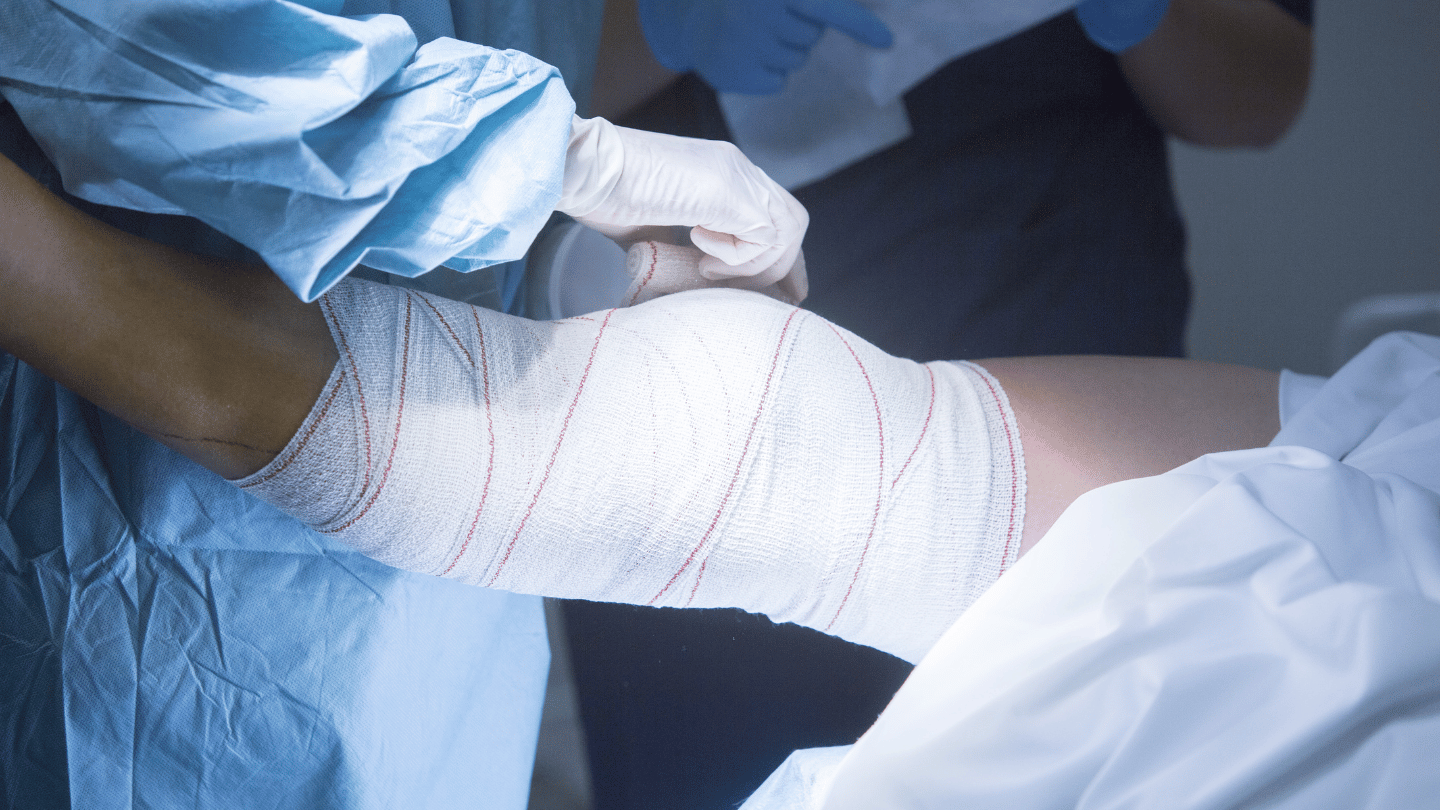

How to prepare for a successful knee surgery: Tips and recommendations

Knee surgery is a procedure that can significantly improve the quality of life for those suffering from injuries or conditions that affect this crucial joint.